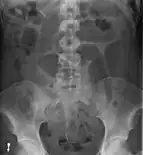

After taking a thorough history, the diagnosis of colonic volvulus is usually easily included in the differential diagnosis. Abdominal plain x-rays are commonly confirmatory for a volvulus, especially if a "bent inner tube" sign or a "coffee bean" sign are seen. These refer to the shape of the air-filled closed loop of colon which forms the volvulus. Should the diagnosis be in doubt, a barium enema may be used to demonstrate a "bird's beak" at the point where the segment of proximal bowel and distal bowel rotate to form the volvulus.